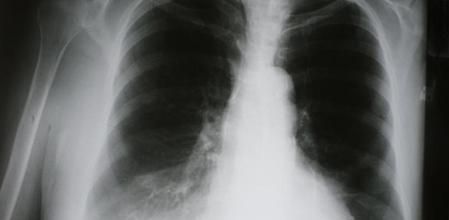

Para diagnosticar las enfermedades relacionadas con la AAT se realizarán, además, radiografías de tórax, pruebas de función respiratoria, una tomografía computerizada TC de tórax y ecografía abdominal.